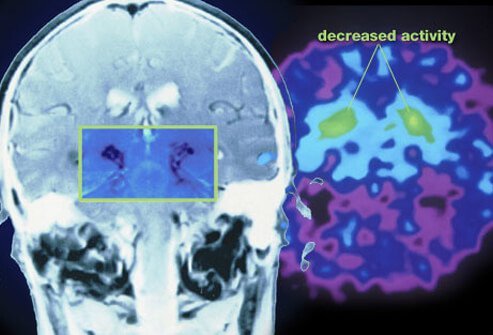

Cells in the substantia nigra, a part of the brainstem that controls movement, slow down and then stop producing dopamine as the cells die. Dopamine helps nerve cells communicate about movement; without the dopamine, body commands about normal movement are disrupted resulting in Parkinson's disease because the brain does not receive the necessary messages about how and when to move. Unfortunately, the ultimate cause of Parkinson's disease, the reason that the cells in the brainstem become altered and die, is not known but researchers suggest that a combination of both genetic and environmental factors cause about 90% of all Parkinson's disease.